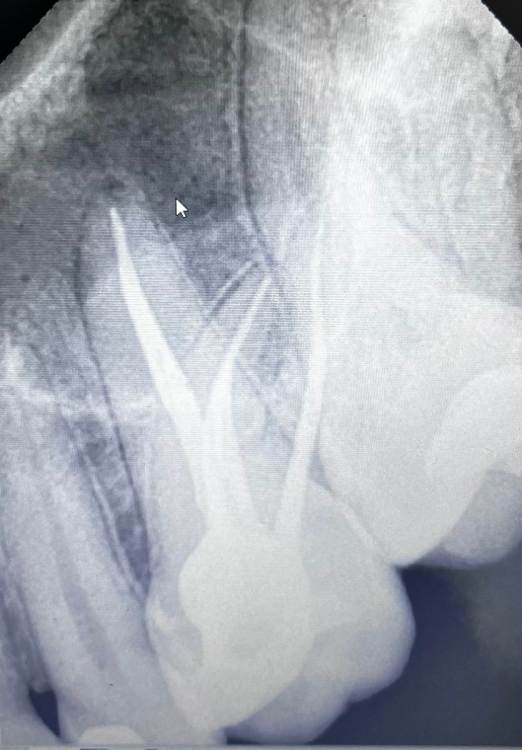

Martin Опубликовано 21 марта, 2023 Поделиться Опубликовано 21 марта, 2023 (изменено) Лечили зуб 26 по поводу пульпита около 2х месяцев назад. И с тех пор он болит при накусывании. Именно он. Суперконтактов нет. Перкуссия безболезненна, так же как и соседних Зубов. В чем может быть причина ? Изменено 21 марта, 2023 пользователем Martin Ссылка на комментарий

red_butler Опубликовано 22 марта, 2023 Поделиться Опубликовано 22 марта, 2023 четвертого канала нет? Ссылка на комментарий

annda Опубликовано 22 марта, 2023 Поделиться Опубликовано 22 марта, 2023 Удивительно, при накусывании болит, а перкуссия прямая и сравнительная безболезненна и отрицательна. Что- то тут не срастается.Либо все- таки есть смещающие контакты на щечных скатах. 1 час назад, red_butler сказал: четвертого канала нет? На снимке видно 4й канал 1 Ссылка на комментарий

Martin Опубликовано 22 марта, 2023 Автор Поделиться Опубликовано 22 марта, 2023 8 часов назад, annda сказал: Удивительно, при накусывании болит, а перкуссия прямая и сравнительная безболезненна и отрицательна. Что- то тут не срастается.Либо все- таки есть смещающие контакты на щечных скатах. На снимке видно 4й канал Вот и я не понимаю как такое возможно, поэтому создал эту тему. Боль при накусывание валика ватного именно на зубе 26, перкуссия отрицательна. Может быть такое, что десна болит? Ссылка на комментарий

red_butler Опубликовано 23 марта, 2023 Поделиться Опубликовано 23 марта, 2023 Мартин, сделайте Кт Ссылка на комментарий